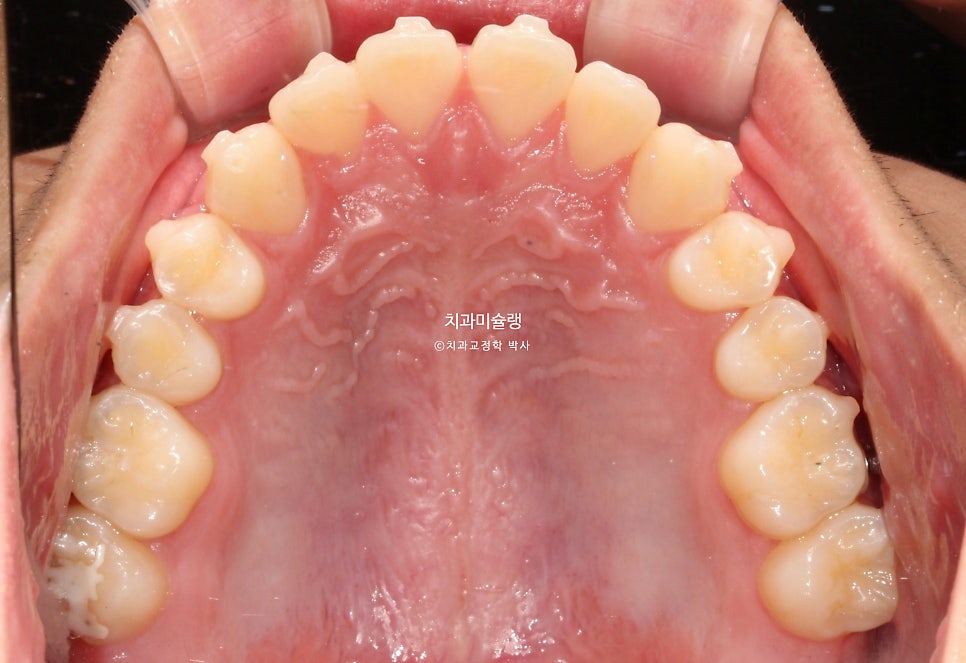

초진 시 구강 상태

제작년 유학중 여름방학을 맞이해 찾아온 만 15세 친구 입니다.

어릴때부터 소아치과에서 주기적으로 체크를 받아오며 교정이 필요없다는 이야기를 들었으나

최근 유학중 1-2년 사이 아래턱이 자란것같아 교정이 필요해보여 내원했습니다.

위 앞니가 벌어져있고 일부 개방교합이 보입니다.

어금니 교합관계는 3급이며 윗니가 아랫니를 덮지 못하는 절단교합 입니다.